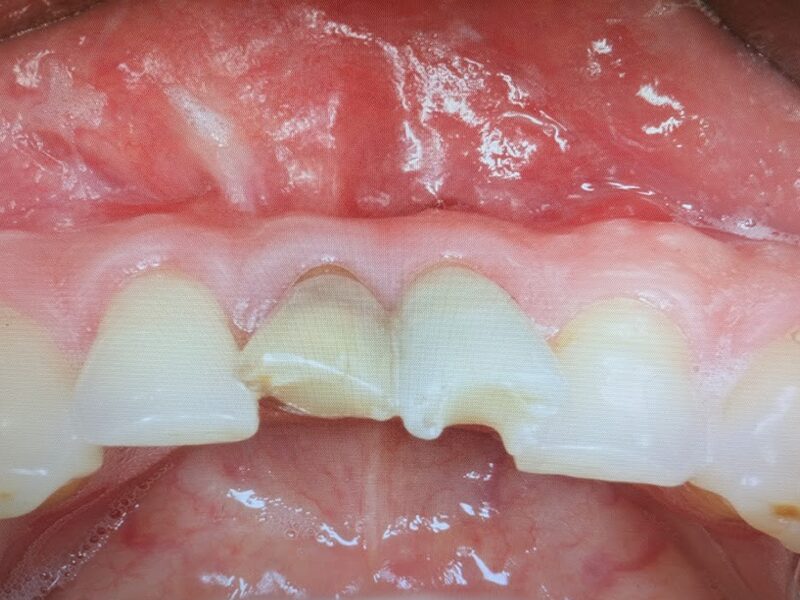

根管治療を行い、歯肉の膿瘍が消失しています。手術の準備が整いましたので手術を実施いたします。

術後3か月です。